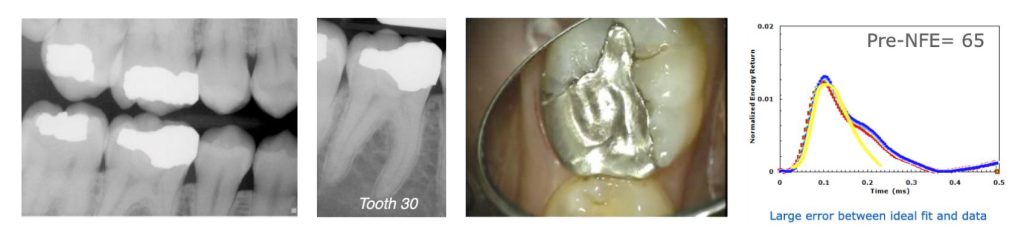

Case 1: Leaking restoration and tooth fracture

Tooth #30 in a 22-year-old woman was slightly sensitive to cold. Radiographs did not show a significant problem, but the ERG (Fig. 2) showed an abnormally shaped graph with a rating of 65. The filling was removed, revealing a leaking alloy marginal opening, with gross decay across the entire intaglio surface of the filling and a tooth fracture on the pulpal floor that ran halfway from the distal marginal ridge to the center of the tooth.

After replacing the leaking restoration with a composite restoration, another QPD measurement was taken and the tooth now registered a rating of 19 (Fig. 3).

(Six years later, the patient moved back to the area and the tooth was tested again. It stabilized at a rating of 21 with no further treatment.)